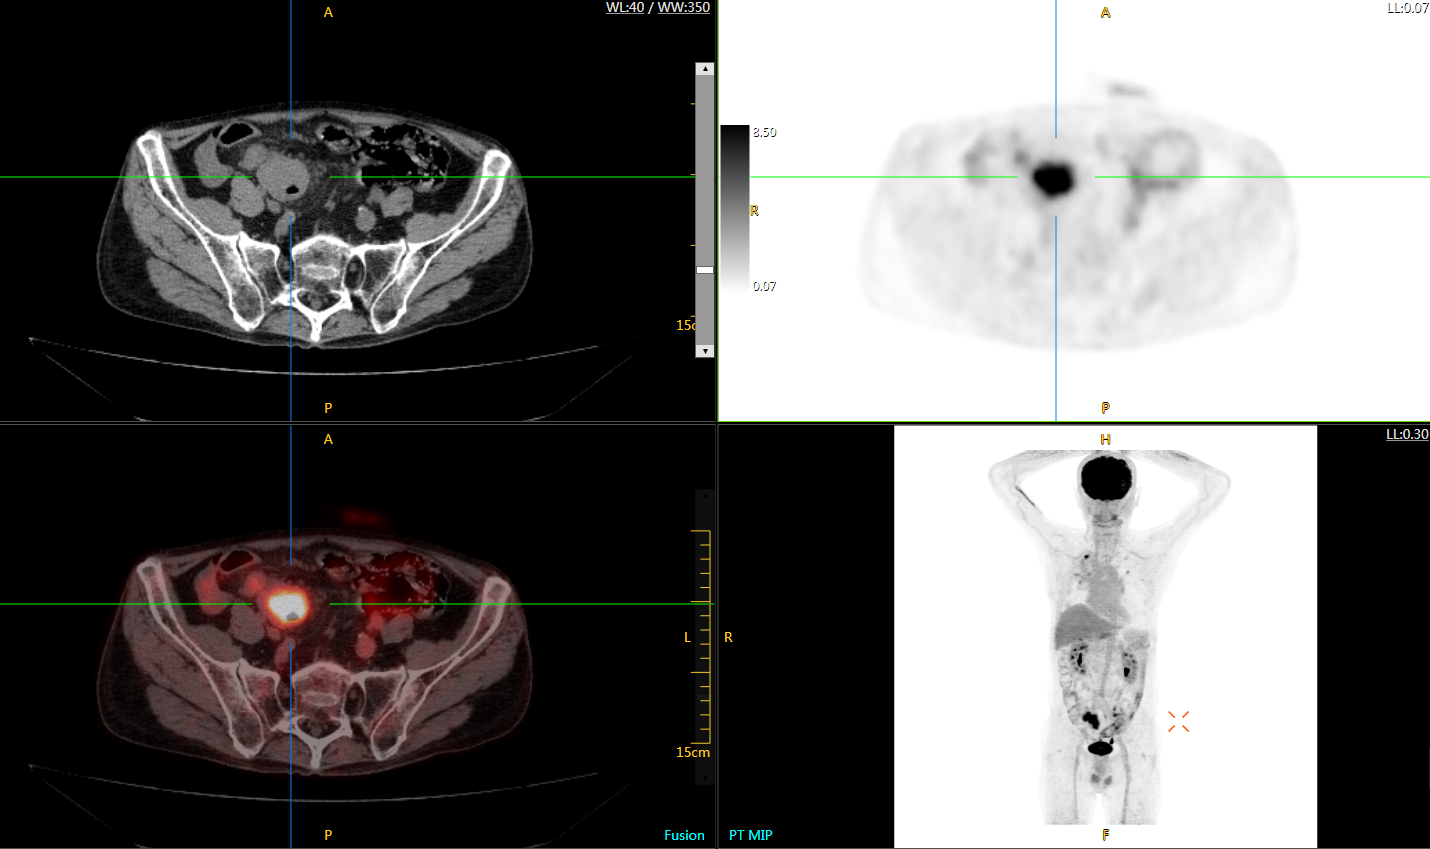

肺癌轉(zhuǎn)移及復發(fā)

患者男性,66歲,七年前發(fā)現(xiàn)右肺肺癌,其間手術(shù)兩次,共切除兩個肺葉,復查;

診斷意見,回腸轉(zhuǎn)移,右肺殘留部復發(fā)